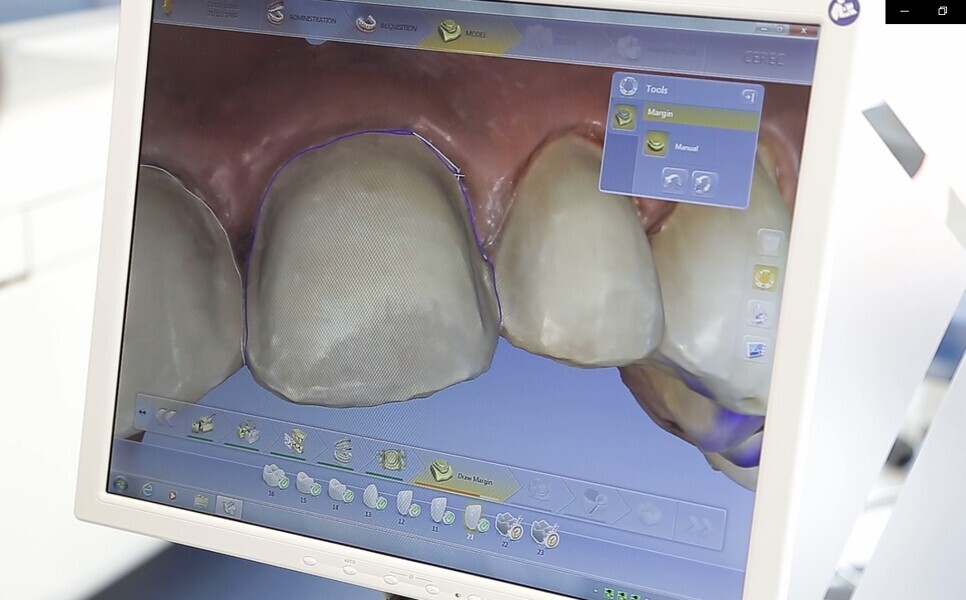

Fig. 20: Digital modelling.

Fig. 21: Final digital ceramic

restorations.